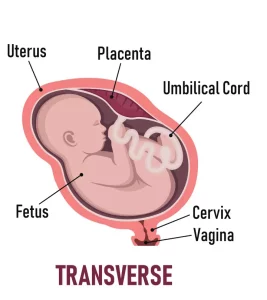

– Transverse lie:

Transverse Lie (Umwana aryamye ku ruhande)

Mu buryo busanzwenanone , umwana aba yicaye mu nda ku murongo uhuza umutwe n’ikibuno (longitudinal lie). Ariko hari igihe umwana aba aryamye ku ruhande, ibi bikitwa transverse lie:

– Icyo bivuze: Umwana aba yicaye mu nda ku buryo umutwe we n’ikibuno bye biri ku mpande zinyuranye z’inyababyeyi, bityo ntibibe biri mu murongo wo gusohoka. Ni nko kuba umwana aryamye ku ruhande mu nda.

– Ingaruka:

– Kubyarira mu buryo busanzwe ntibishoboka, kuko inkondo y’umura iba itabonye umutwe cyangwa ikibuno mu mwanya wo gusohoka.

– Akenshi bisaba kubagwa (cesarean section) kugira ngo umwana avuke neza.